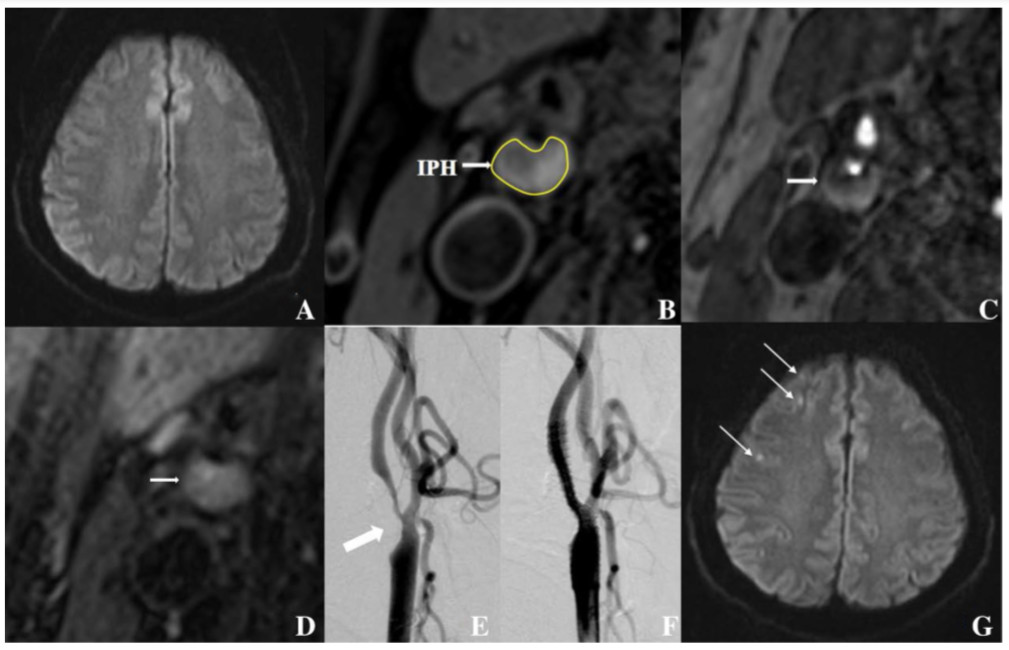

A:CAS术前, 脑DWI

B、C、D分别对应T1,T2,3D TOF 序列血管图像,可见有明显斑块内出血(IPH)

E、F为CAS术前后血管造影图像,可见术后血管已经再通

G:CAS术后, 脑DWI,可见有新的缺血性病变